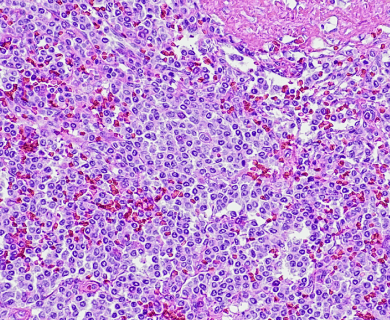

Pathologists look at tumor and tissue samples and determine what cells they can see. If the majority of cells from your mesothelioma sample are epithelioid cells, your mesothelioma subtype is determined to be epithelioid mesothelioma.

A tissue biopsy is the only way to diagnose epithelioid mesothelioma. This procedure involves taking samples of suspicious tissue. Pathologists examine the tissue samples under a microscope to identify specific cell characteristics.

Epithelioid mesothelioma cells clump together in groups and don’t tend to travel. These cell types are less likely to spread to other areas of the body. When a pathologist confirms the presence of specific cancer cells, an accurate diagnosis of your mesothelioma type can be made.

The tool or technique for studying cancer tissues is called immunohistochemistry. Pathologists look at stained samples, testing for certain proteins linked to epithelial cells. If pathologists find proteins from other cancers, they’ll rule out epithelioid mesothelioma.

The proteins that help doctors identify epithelioid mesothelioma from different types of cancer include: calretinin, D2-40, keratin 5/6, podoplanin and WT-1 protein. An official diagnosis depends on more than just immunohistochemistry. It also considers the tumor’s appearance, location and cell traits.

While epithelioid is a subtype of mesothelioma, there are further subtypes of the epithelioid type. Pathologists can identify these cell subtypes with immunohistochemistry.

Epithelioid mesothelioma has a better prognosis than other subtypes, but some epithelioid cell subtypes also have better prognoses than others. For example, adenomatoid cells are associated with a better mesothelioma survival rate.